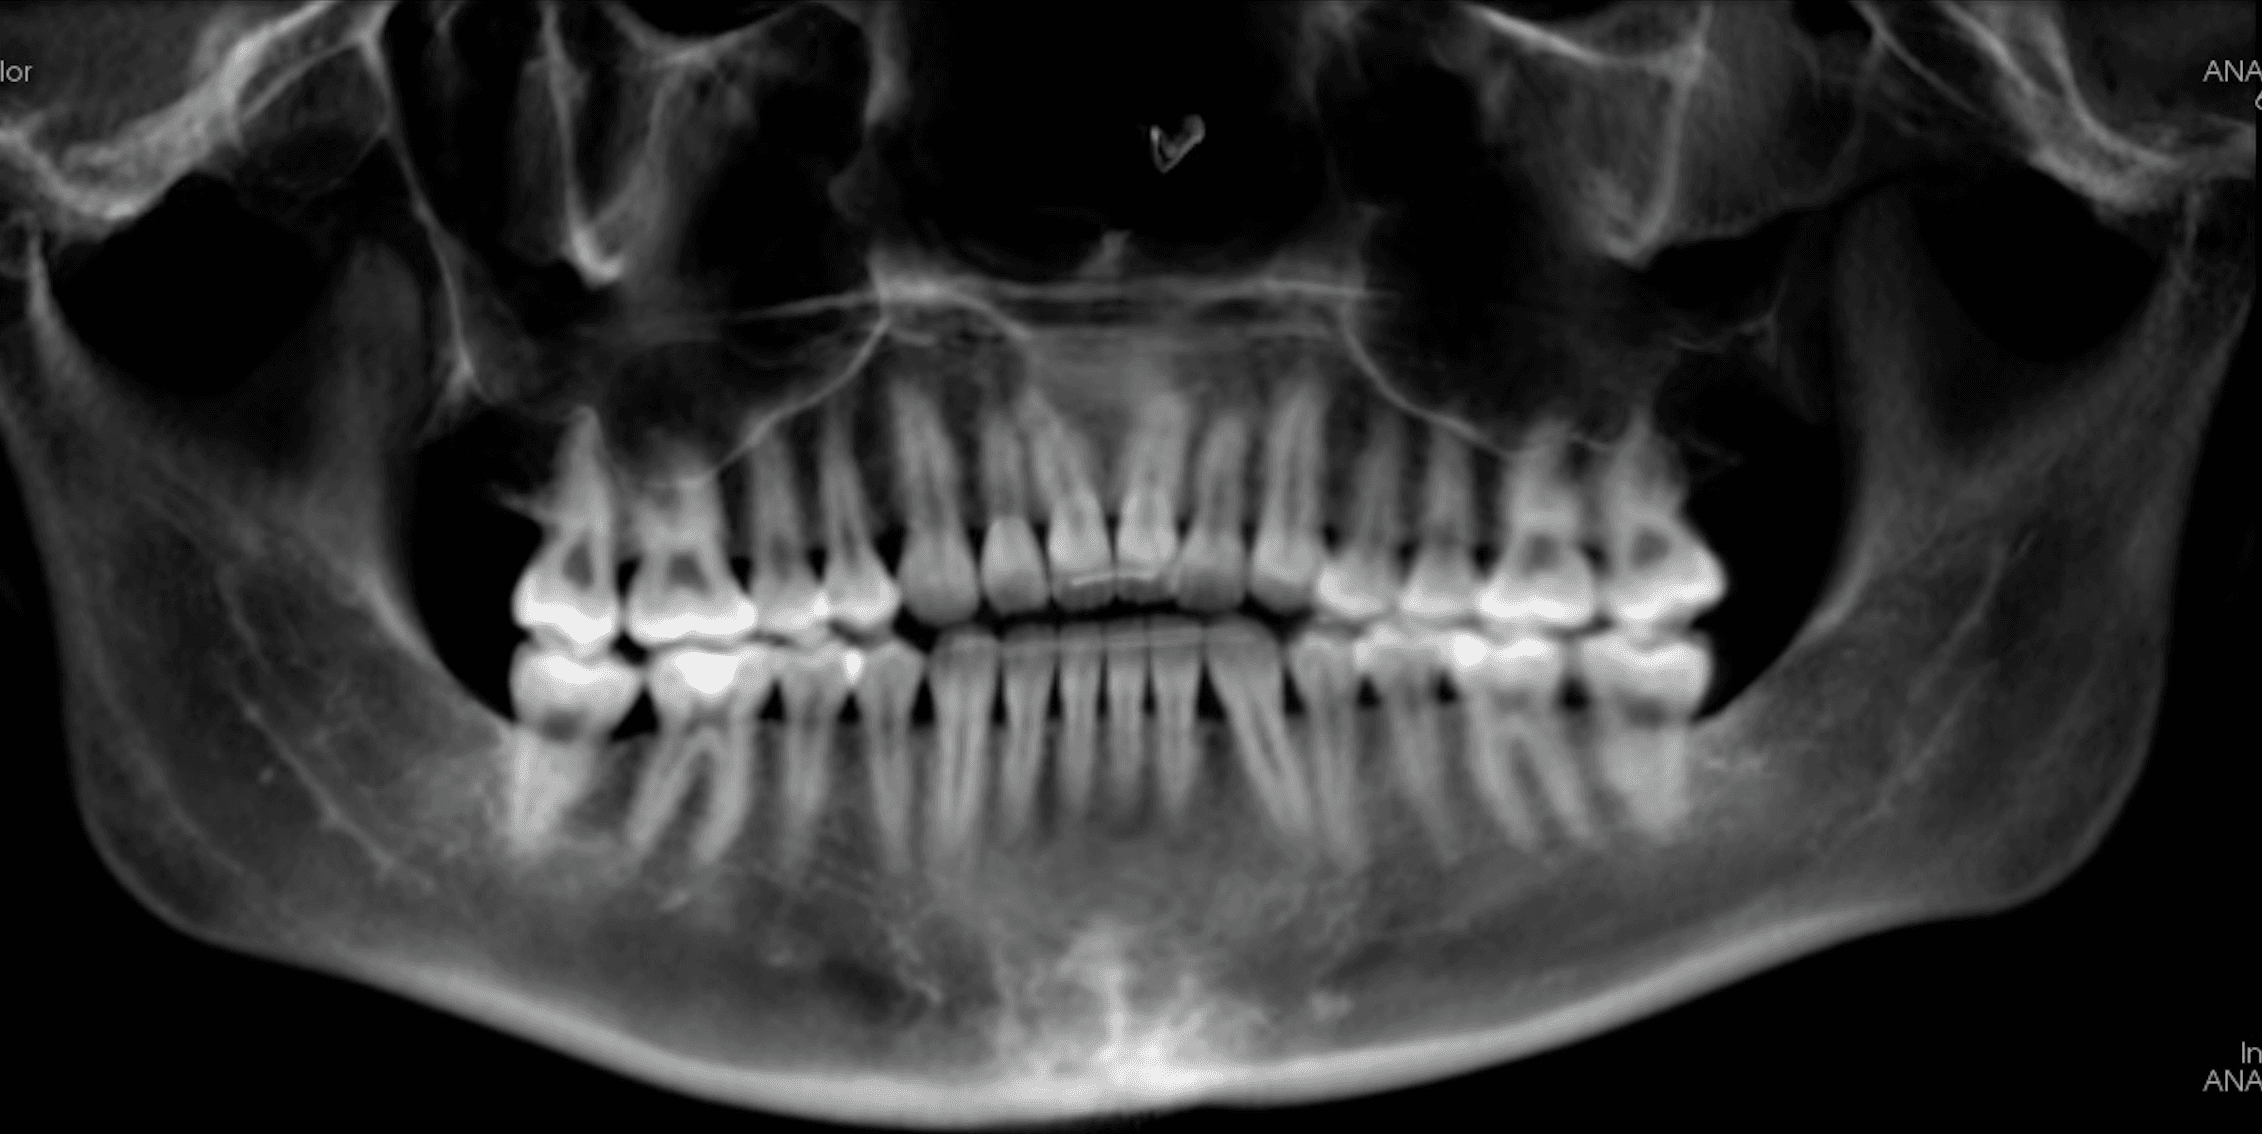

Initial treatment

X-RAYS